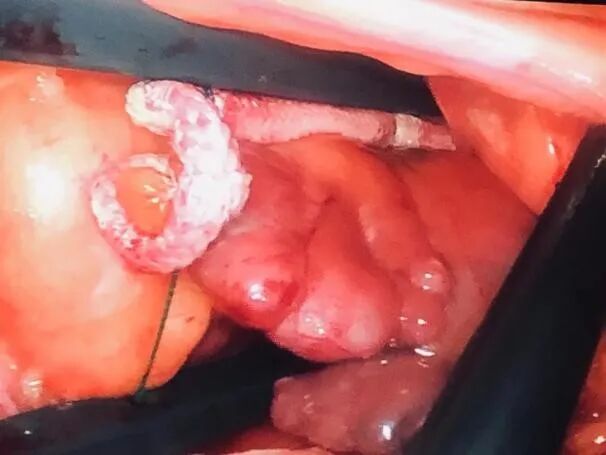

手术直播(十四):全胸腔镜二尖瓣置换术

患者为58岁男性,诊断为感染性心内膜炎、二尖瓣赘生物、二尖瓣重度关闭不全、心功能III级、高血压、2型糖尿病。入院后心脏超声示:感染性心内膜炎,二尖瓣前、后叶赘生物附着(A1区左房面1.4*1.0cm附着,P1区左房面2.0*0.7cm附着),前叶A1区穿孔(0.3cm),二尖瓣大量反流,左房、左室明显增大(左室6.0*6.8cm),左室壁稍增厚,EF:70%。

姜胜利教授计划行全胸腔镜二尖瓣手术,争取成形。手术在2.5cm主操作孔中完成,进入左房后发现二尖瓣赘生物和瓣叶受累比术前超声显示的更加广泛,整个A1P1区瓣叶、瓣下结构及部分P2区组织都受累,赘生物对瓣叶侵蚀严重、距离瓣环近,成形难度极大,且可能效果不佳,正所谓'巧妇难为无米之炊',虽然术前手术预案是尽力为患者进行二尖瓣的修复,但是赘生物已经严重侵蚀瓣叶瓣环结构,最终为患者进行二尖瓣置换,精准切除受累瓣膜组织后,植入27mm生物瓣!手术过程非常顺利。最后姜胜利教授还强调了感染性心内膜炎患者一定要加强术后抗感染治疗。